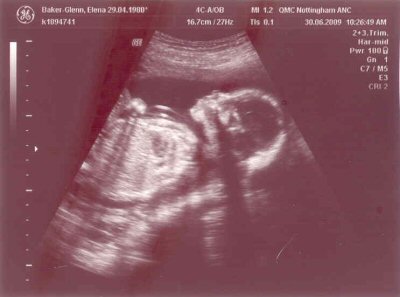

- 20 week scan

- The scan photos shown below were from the 20 week scan which was done on the 30th June 2009 when the gestational age was 21 + 2 weeks.